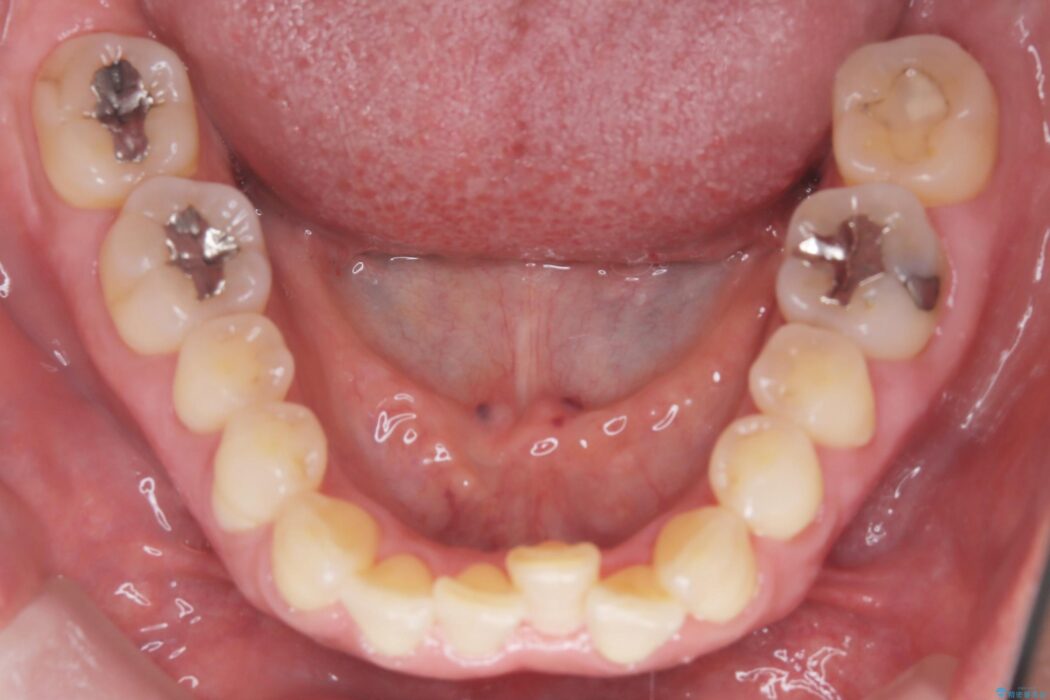

前歯のガタつきが気になるとご来院された患者様です。

精密検査の結果、抜歯は不要、わずかなスペースを確保することで歯並びを整えられると診断しました。

スペース確保は、奥歯を少し後ろへ動かす遠心移動と、歯の側面をわずかに削るIPRを併用し、約1年間での治療完了を目指しました。